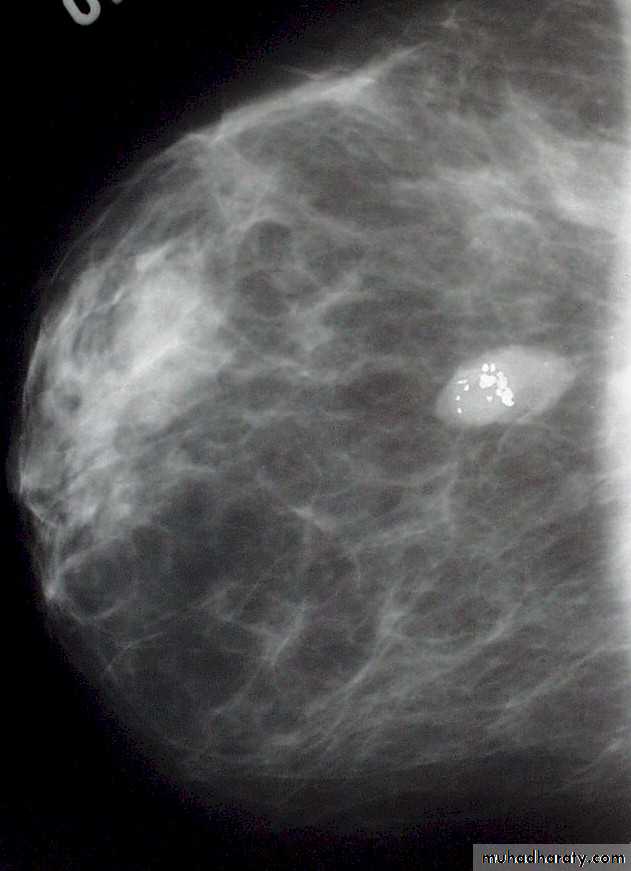

Malignant microcalcification